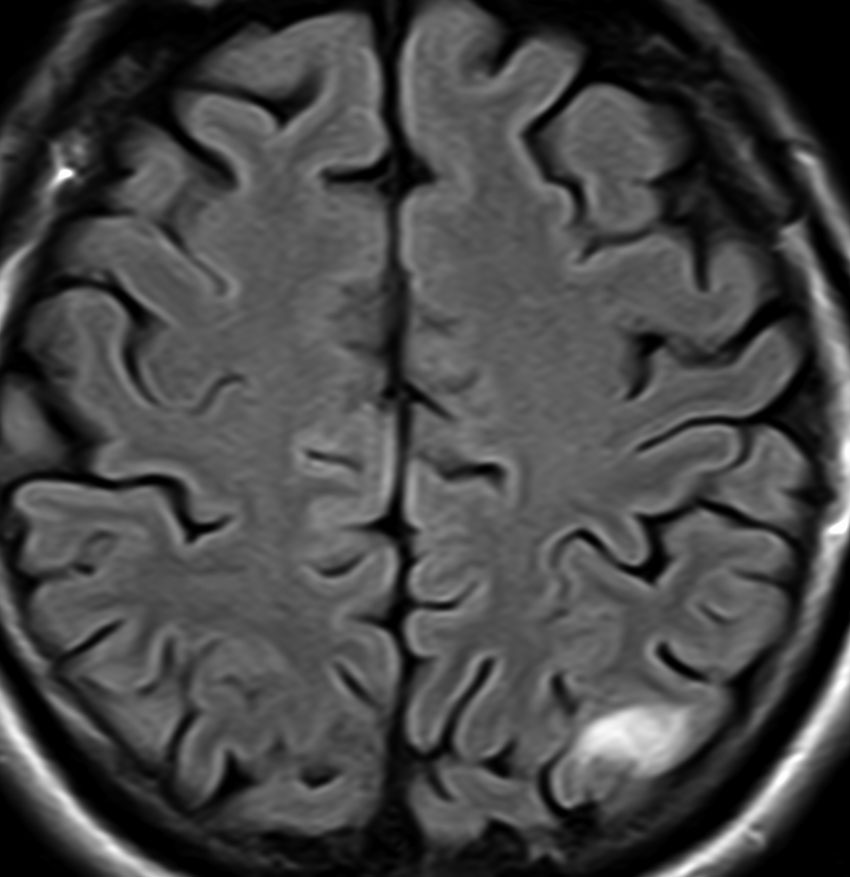

フレア画像です。左上前頭回の星細胞腫ですが,境界がとてもはっきりしていて限局性 localized single gyrus glioma です。びまん性 diffuseには見えません。IDH1の変異があり,1p/19qの欠失はないので星細胞腫グレード2です。上の例とは全く違う臨床像を示しますが,分子病理でも区別はつきません。頑張って早めに全摘出して治してしまった方がいいタイプです。再発を避けるために,supratotal resectionと言って,周囲の正常脳組織も10mmくらい余分に摘出します。